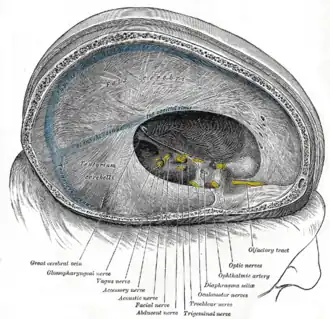

Твёрдая мозговая оболочка и её отростки Синусы основания черепа

Синусы основания черепа